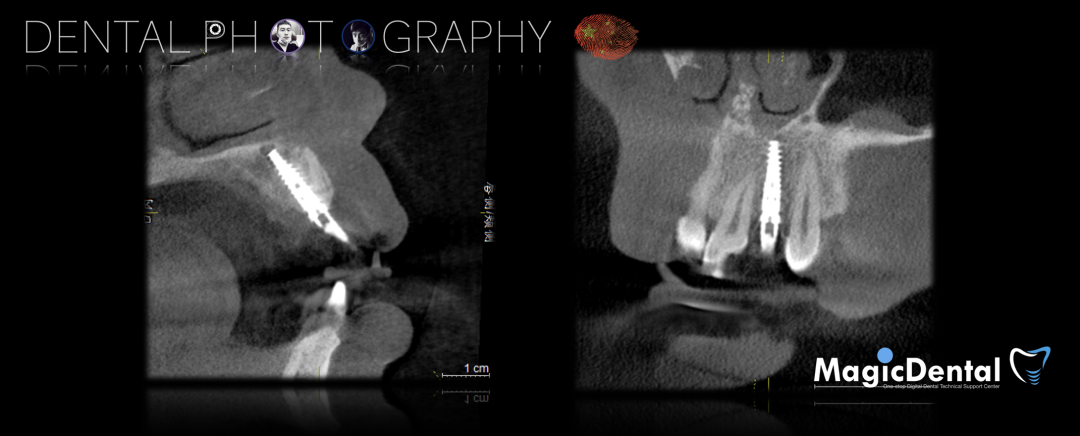

术前CBCT

22缺失,且牙槽骨唇颚侧宽度较窄,38,48近中阻生。

治疗计划:水平骨增量,拔除四区近中阻生智齿,下颌升支外斜线处取块状骨,移植骨块至受区(22唇侧),种植修复22缺失牙。

术后五个月复查及CBCT检查

术后3个月CBCT及X线片。